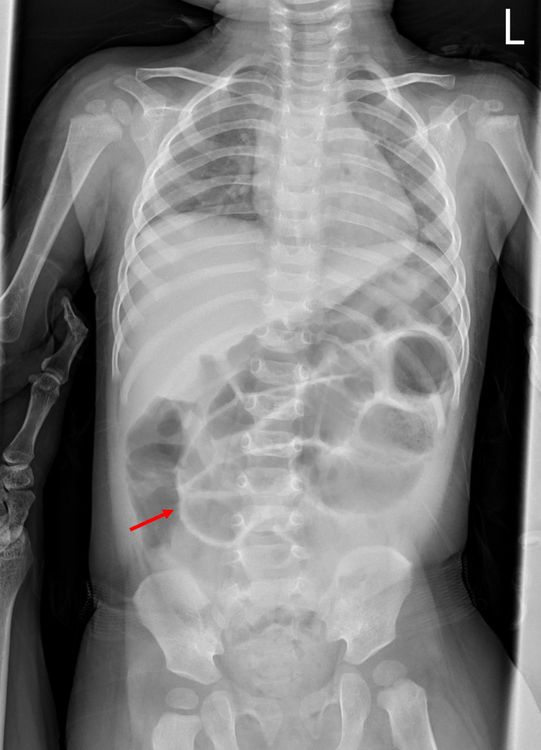

在X光片中,可看到女童因腸穿孔、腹腔內充斥不該有的空氣,造成腸壁在影像中異常明顯(如箭頭)。張鈺堂醫師提供

陳威翰則表示,這名1歲3個月女童,在家發燒逾39度且嘔吐,被家人帶至急診,經抽血發現白血球數高,腹部有壓痛感,X光與電腦斷層影像,則發現腹腔內有不該有的氣體,高度懷疑是腸穿孔與腹膜炎,隨即推進手術室開刀。